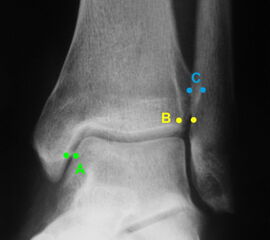

Röntgen

Röntgenaufnahmen dienen primär dem Ausschluss einer knöchernen Verletzung. Die Beurteilung der Geometrie der Malleolengabel kann einen ersten Hinweis auf eine Syndesmosenverletzung liefern. Die notwendigen Röntgenaufnahmen umfassen das Sprunggelenk anterior-posterior, lateral und in 20° Innenrotation (Mortise view). Zur Beurteilung der Syndesmose sind verschieden Parameter in der Mortise view beschrieben. Zu diesen zählen der tibiofibulare Clearspace, der mediale Clearspace, sowie die Überlappung der distalen Fibula und Tibia im Bereich der Incisura (Abbildung 2). Der Tibiofibulare Clearspace wird als verlässlichster Indikator für eine Syndesmosenverletzung gesehen, da er nicht signifikant von der tibialen Rotation beeinflusst wird 32. Er wird 1 cm proximal des Tibiaplafonds gemessen und sollte weniger als 6mm betragen 33. Jede Messung, die diesen Wert übersteigt, stellt einen Hinweis für eine Syndesmosenverletzung dar. Eine tibiofibulare Überlappung von 6 mm oder mehr in der AP Aufnahme, sowie mehr als 1 mm in der Mortise View Aufnahme gelten als physiologisch 33. Der mediale Clearspace sollte nicht mehr als 4 mm betragen 34.

Abbildung 3 zeigt ein Sprunggelenk nach Syndesmosenverletzung mit einem erweiterten Tibiofibularen Clearspace.